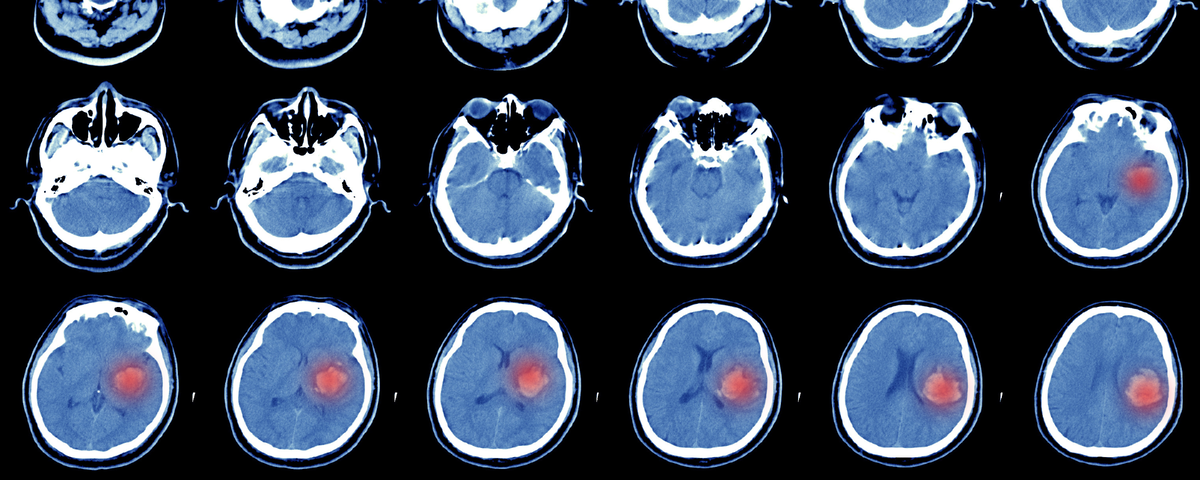

Геморрагический инсульт – это острое нарушение мозгового кровообращения, вызванное разрывом сосуда и кровоизлиянием в мозг. В отличие от ишемического инсульта, при геморрагическом происходит прямое повреждение тканей из-за излившейся крови.

Это наиболее опасный тип инсульта, с высокой летальностью и тяжелыми последствиями. Летальность от геморрагического инсульта достигает 40-50%, а инвалидность развивается у 70-75% выживших.

Геморрагический инсульт составляет 10-15% от всех видов нарушения мозгового кровообращения. Средний возраст пациентов – 60-65 лет. Риск развития геморрагического инсульта значительно повышается после 55 лет и удваивается с каждым последующим десятилетием.

ВИДЫ ГЕМОРРАГИЧЕСКОГО ИНСУЛЬТА

· Внутримозговое кровоизлияние (80% случаев)

Кровь изливается непосредственно в ткань мозга, образуя гематому. Чаще всего возникает из-за гипертонии, амилоидоза или сосудистых аномалий.

· Субарахноидальное кровоизлияние (20% случаев)

Кровь попадает в пространство между мозгом и его оболочками. Основная причина – разрыв аневризмы или артериовенозной мальформации (АВМ).